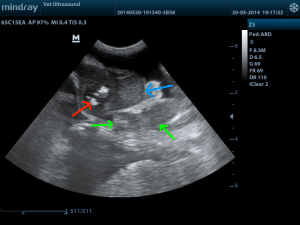

κόκκινο βέλος εντερικό περιεχόμενο, μπλέ βέλος μάζα με απώλεια της χαρακτηριστικής δομής του λεπτού εντέρου., πράσινα βέλη διογκωμένος μεσεντέριος λεμφαδένας.